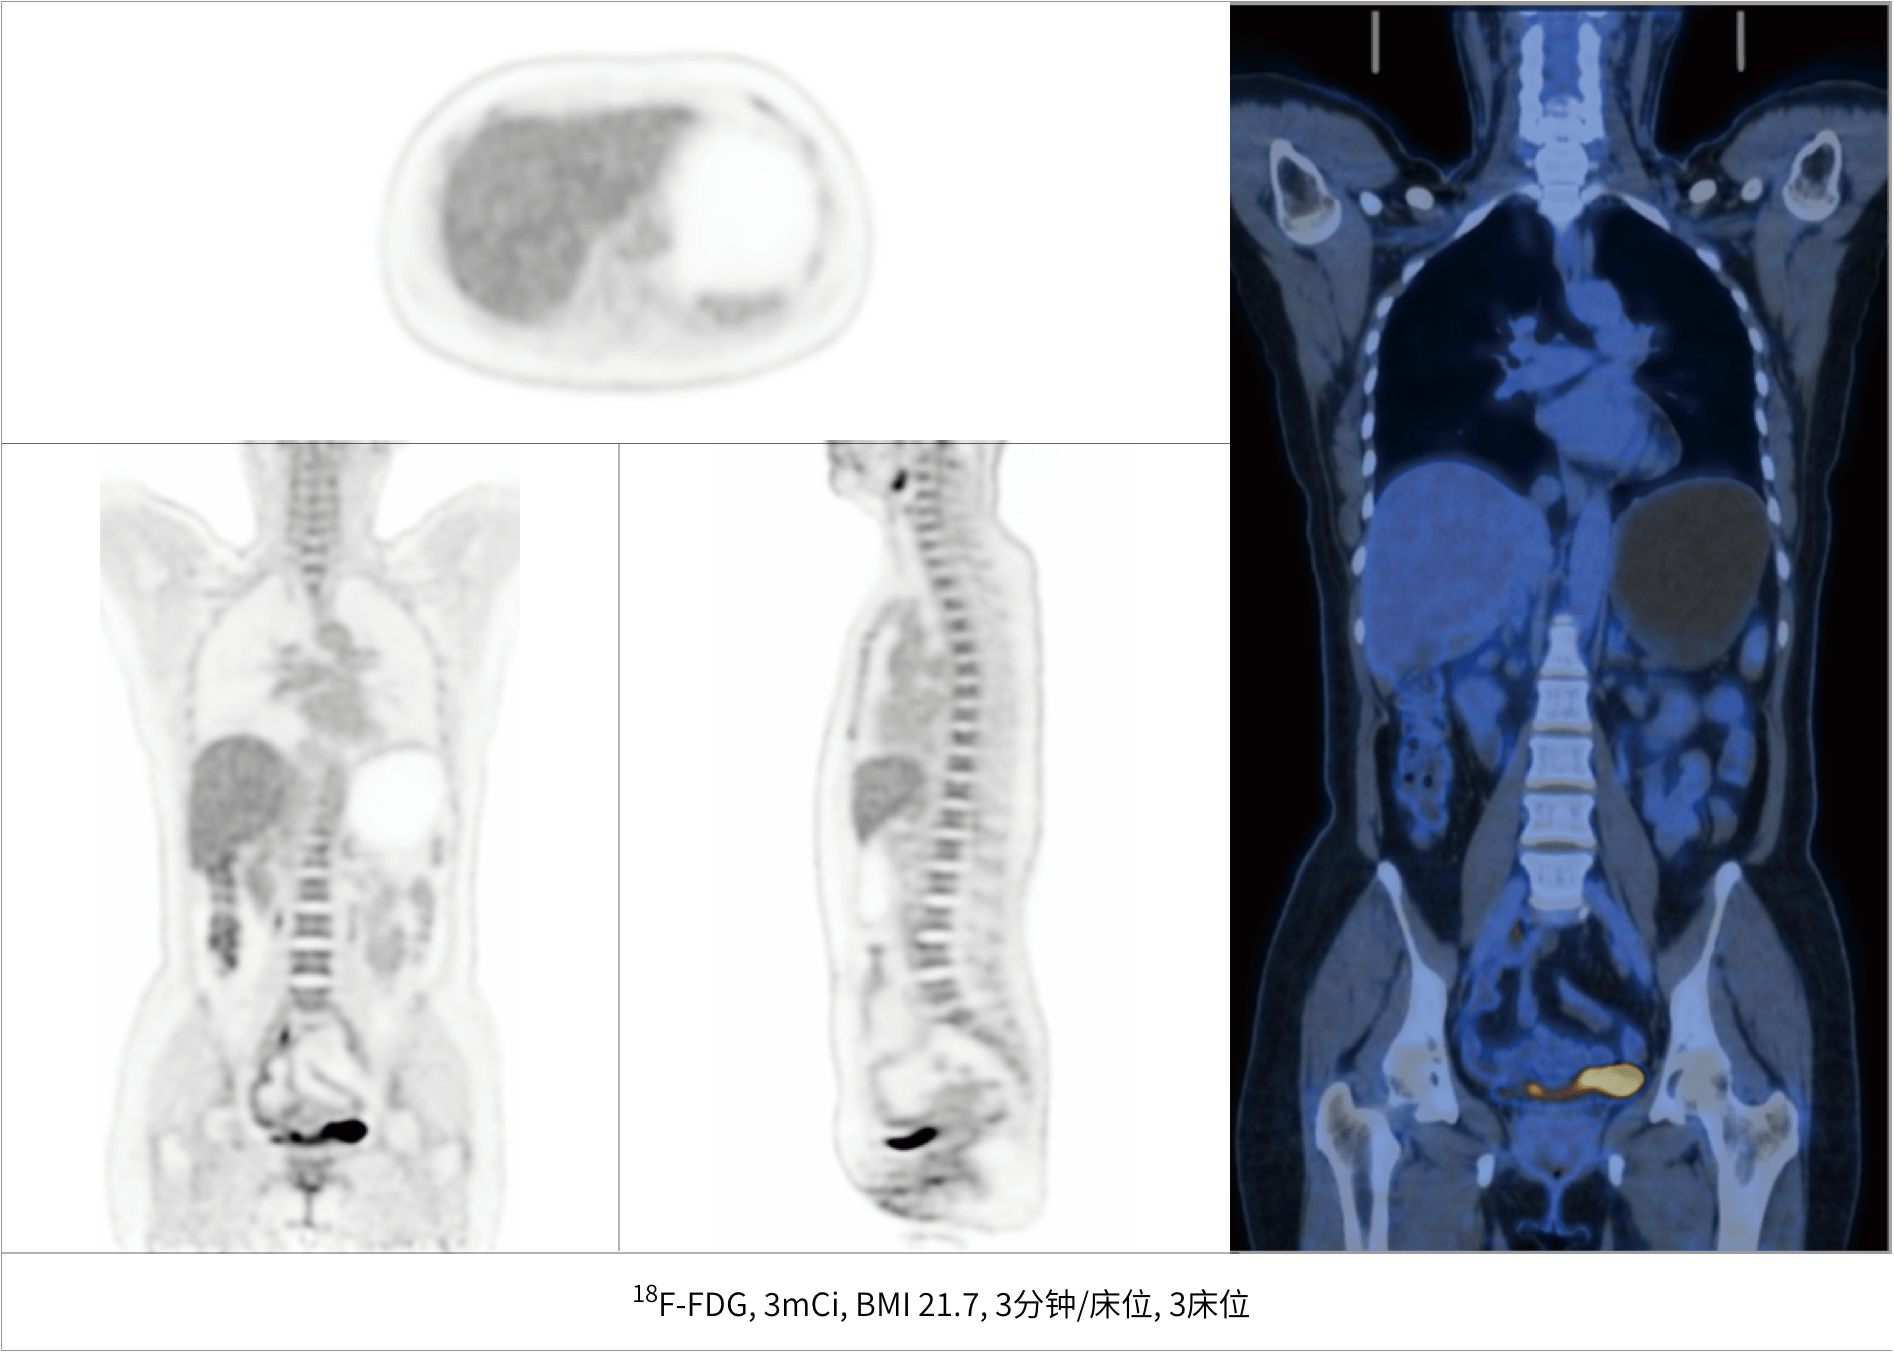

3床位

快速临床扫描

5分钟

提升患者检查体验